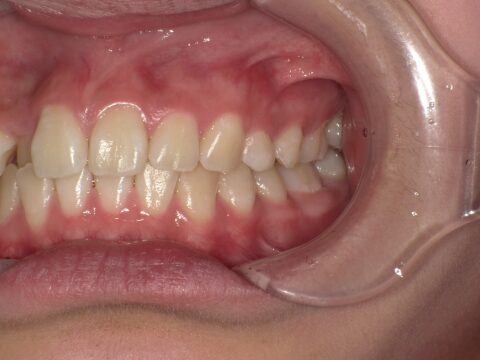

クロスバイト

治療前

ガタガタを主訴に当院を受診され、右上2番にクロスバイトを認めました。IPRを使用してマウスピース型矯正装置(インビザライン)を使用し改善を行いました。